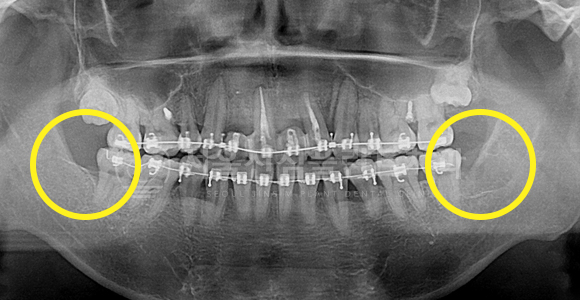

바르게 맹출된 사랑니 발치 + 매복 사랑니 발치

BEFORE

AFTER

사랑니가 바르고 정상적으로 맹출 되어도 구강 관리가 어려워 충치 이환도가 높아짐으로 예방적으로 발치하는 것을 추천해 드립니다.